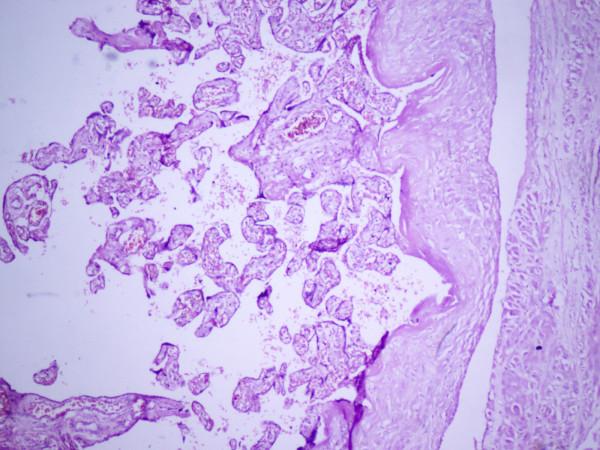

Abdominal pregnancy is a rare event, but one that represents a grave risk to the health of the pregnant woman. An abdominal pregnancy is defined as an ectopic pregnancy that implants in the peritoneal cavity. Early abdominal pregnancy is self-limited by hemorrhage from trophoblastic invasion with complete abortion of the gestational sac that leaves a discrete crater. Advanced abdominal pregnancy is a rare event, with high fetal and maternal morbidity and mortality.

This is a case report of a 22-year-old primigravida with an abdominal pregnancy from a ruptured rudimentary horn. She was diagnosed as a case of term pregnancy with placenta previa with a transverse fetal lie and cervical fibroid and was prepared for an elective cesarean section. Intra-operatively, a live term female baby was extracted from the peritoneal cavity and it turned out to be an abdominal pregnancy from a ruptured rudimentary horn of a unicornuate uterus, which is a very rare condition. Mother and baby were in good condition after such a catastrophic event.